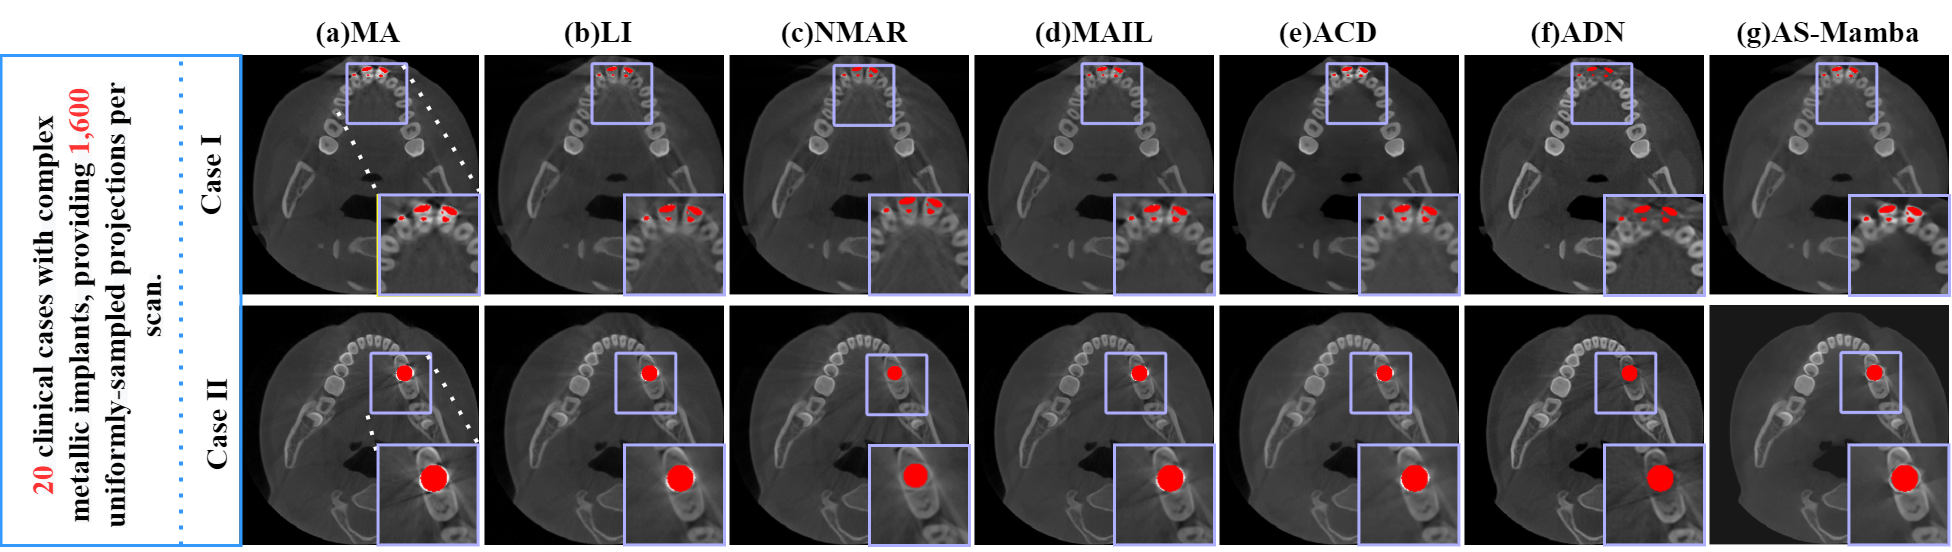

4.1.2 Clinical CBCT Data

We evaluated our method on two clinical dental datasets. The first, provided by the First Affiliated Hospital of Nanchang University, contains 20 cases with 200 slices each. The sinograms () cover 1600 projections over . These images feature varied metal implants without other anatomical abnormalities, ensuring reliable assessment(No. IIT [2025] LLS No. 482-1).

We present a visual comparison of different MAR methods on simulated DeepLesion data in Fig. 6, featuring three distinct implant sizes with overlaid metal masks and magnified ROIs. The original images exhibit severe dark band artifacts between the implants. LI, NMAR and even the deep learning-based MAIL, while reducing conspicuous streaks, often introduce secondary artifacts and loss of detail due to sinogram discontinuities. While deep learning approaches generally outperform traditional ones, methods like InDuDoNet+ tend to produce overly smooth results lacking geometric constraints. For larger implants, ACDNet and MAIL improve upon ADN but still leave residual artifacts. In contrast, our proposed method effectively suppresses the vast majority of artifacts while accurately preserving fine anatomical details.

4.4 Performance on Clinical CBCT Data

To validate clinical applicability, we evaluated AS-Mamba on real-world dental CBCT scans. Since ground truth is unavailable for clinical data, we employed three objective metrics: Standard Deviation (STD) to measure tissue smoothness, Contrast-to-Noise Ratio (CNR) to assess structural clarity, and a subjective Clinical Score.

The visual comparison on the LargeV dataset is presented in Fig. 8, where AS-Mamba demonstrates its superior capability in tracing and suppressing directional metal streaks via the Mamba scan mechanism, while avoiding the blurring common in traditional methods or the over-smoothing seen in existing deep learning models. To further assess clinical utility, Fig. 9 and Table 2 provide the evaluation on real-world dental CBCT scans from the First Affiliated Hospital of Nanchang University. AS-Mamba achieves the best quantitative results with the lowest STD of HU and the highest CNR of 0.98, indicating effective artifact removal and contrast recovery. Most importantly, our method received the highest Clinical Score of 4.00 from specialists, confirming its ability to provide the most reliable anatomical details for clinical diagnosis.